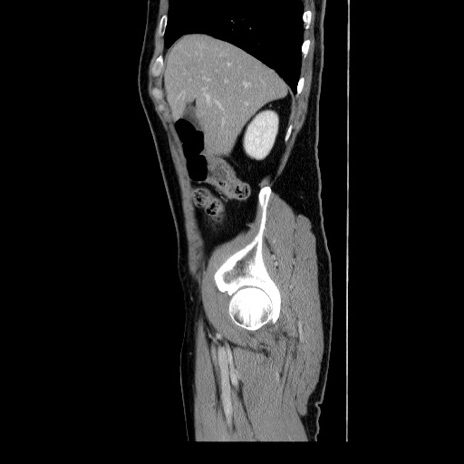

冠状断像